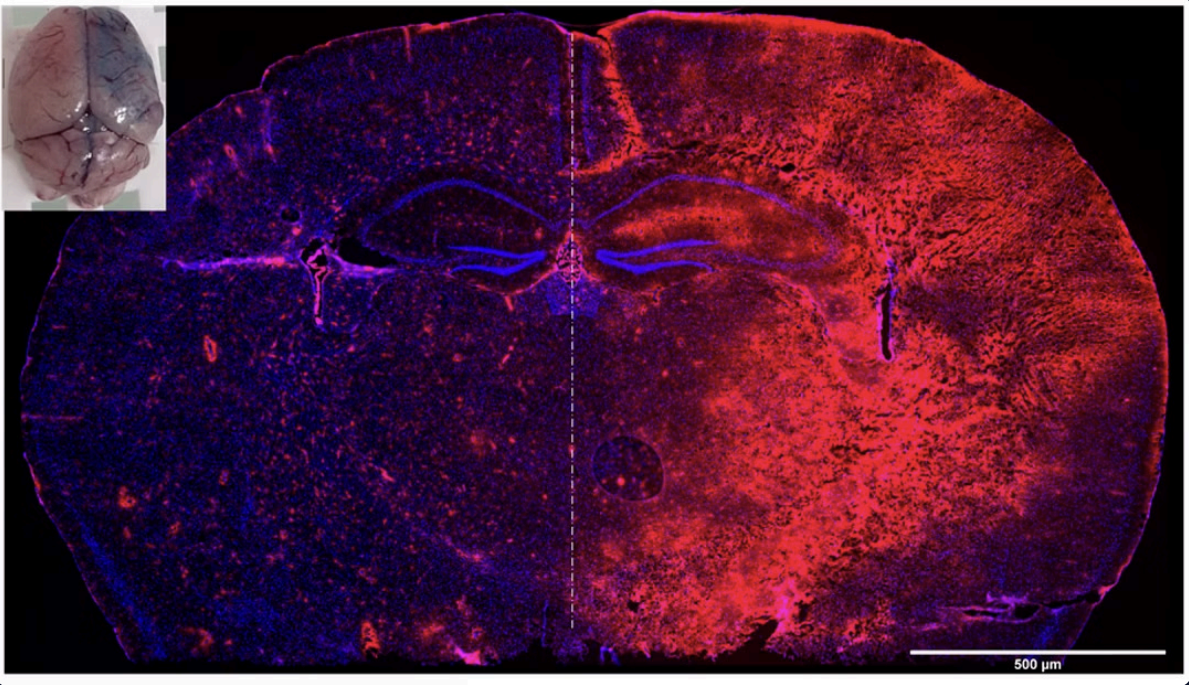

InnoSer’s in-house validation of the TDP-43 mouse model included a qualitative assessment (performed in the same staining session and imaged under the same conditions) of TDP-43 (mouse and human TDP-43) cellular localisation, confirming an increase in the level of both cytoplasmic and nuclear TDP-43 compared to non-transgenic littermates. Note: Non-transgenic TDP-43 littermates show faint nuclear TDP-43 signal due to the presence of endogenous mouse TDP-43.

The single transgenic TDP-43(Q331K) mouse model develops robust motor neuron disease pathophysiology features in the absence of overt cytoplasmic mislocalization and cytoplasmic TDP-43 aggregates/ inclusions and TDP-43 nuclear clearing, in line with literature (Arnold et al., 2013; Watkins et al., 2015; Mitchel et al., 2015) and other single transgenic TDP-43 mouse models such as the TAR6/6 TDP-43 mouse model (Wils et al., 2010; Scherz et al., 2018). Cytoplasmic aggregation of TDP-43 into insoluble inclusions in cortical and spinal neurons has been observed in this mouse model at 24 months of age (see supplementary figure 4 in Mitchel et al., 2015), making it more suitable for longitudinal studies examining rescue of motor function deficits in the setting of ALS and/or FTD.

This TDP-43 mouse model has minimal overexpression of the human TARDBP gene (Watkins et al., 2021; Mitchell et al., 2015); therefore, this single transgenic TDP-43 mouse model shows cytoplasmic TDP-43 accumulation, but no visible cytoplasmic TDP-43 aggregates and nuclear clearing of TDP-43. Consistent with this, cytoplasmic aggregation of TDP-43 into insoluble inclusions in cortical and spinal neurons has been observed in this mouse model at 24 months of age (See figure 5 of Mitchel et al., 2015), making this model more suitable for studying progressive motor deficits and early ALS/FTD-related pathophysiology.